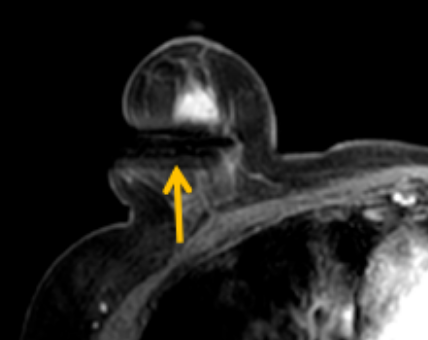

陳寶瑩評估圖像后發(fā)現(xiàn)病變?yōu)閮H僅在磁共振增強時顯示,為非腫塊樣病變,比較散,必須取得足夠多的組織才能確保病理檢查的準確性,常用的核芯針活檢獲取的組織較少,因此最終確定了磁共振引導下行真空輔助抽吸旋切活檢。取得患者及家屬認可后,陳寶瑩帶領團隊開始進行術(shù)前準備。

針對患者乳房小固定難度大這一問題,陳寶瑩通過巧妙體位和固定器的調(diào)整,順利固定好乳房。經(jīng)過磁共振多模態(tài)掃描,陳寶瑩找出病變活性成分相對集中區(qū)域,精準確定穿刺路徑,置入引導針、旋切針,到位后多角度旋切取出足量組織,拔除旋切針后即時行磁共振掃描,精準取得組織且術(shù)區(qū)出血很少,遂加壓包扎,整個過程非常順利,旋切活檢后患者回家休息。兩天后隨訪,李女士沒有任何不適,五天后皮膚上幾毫米的小切口已經(jīng)愈合。最終病理結(jié)果證實為乳腺導管原位癌,為早期乳腺癌,為患者后續(xù)針對性治療奠定了基礎。